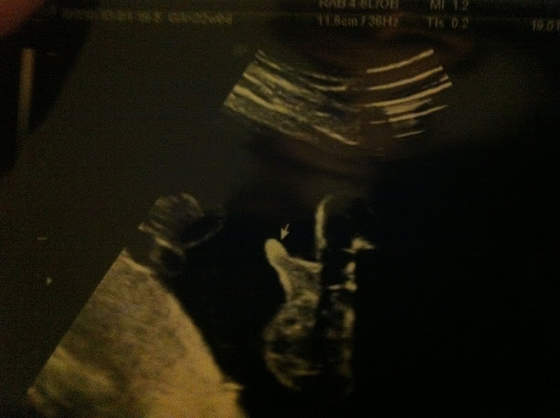

mam pytanie, myślicie że warto iść na usg 4 d, w 26 tygodniu ciąży? Miałam nie iść, ale mąż ma imieniny w piątek i pomyślałam, że w związku z tym, że ani razu nie był ze mną na usg w ramach prezentu pójdziemy na 4 D obejrzeć wspólnie nasz skarb. Tylko czytałam, że warto iść albo do 22 tyd albo dopiero po 30, a ja tak w środku jestem i mam dylemat.